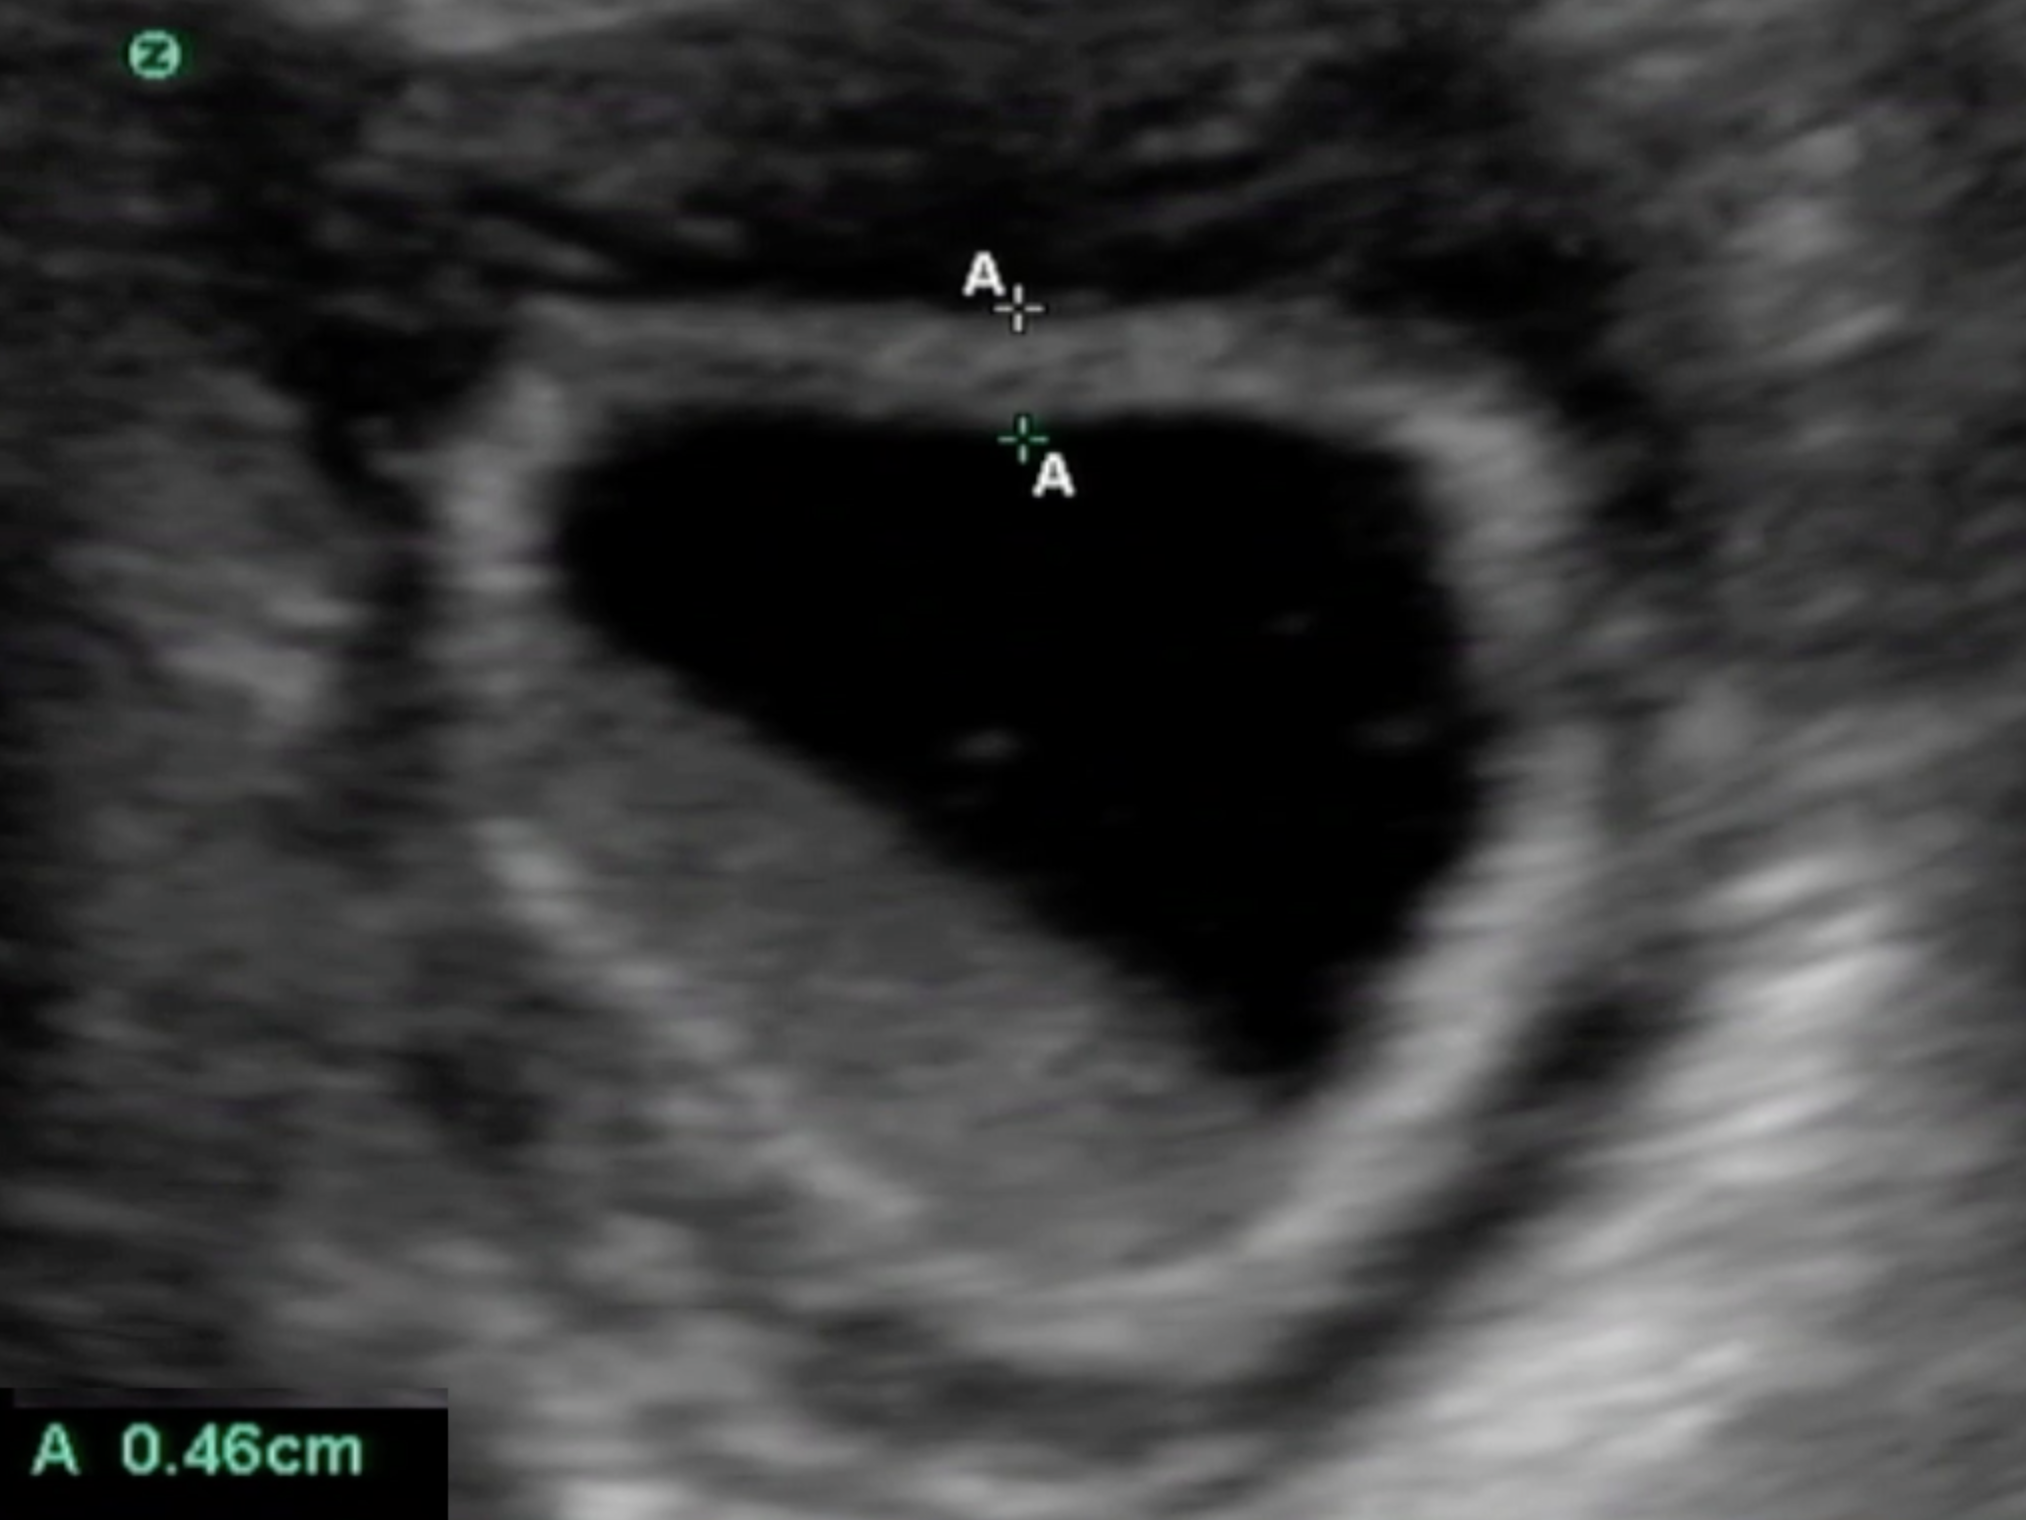

Gallbladder Wall Thickness Image

A - A: Measurement of wall thickness